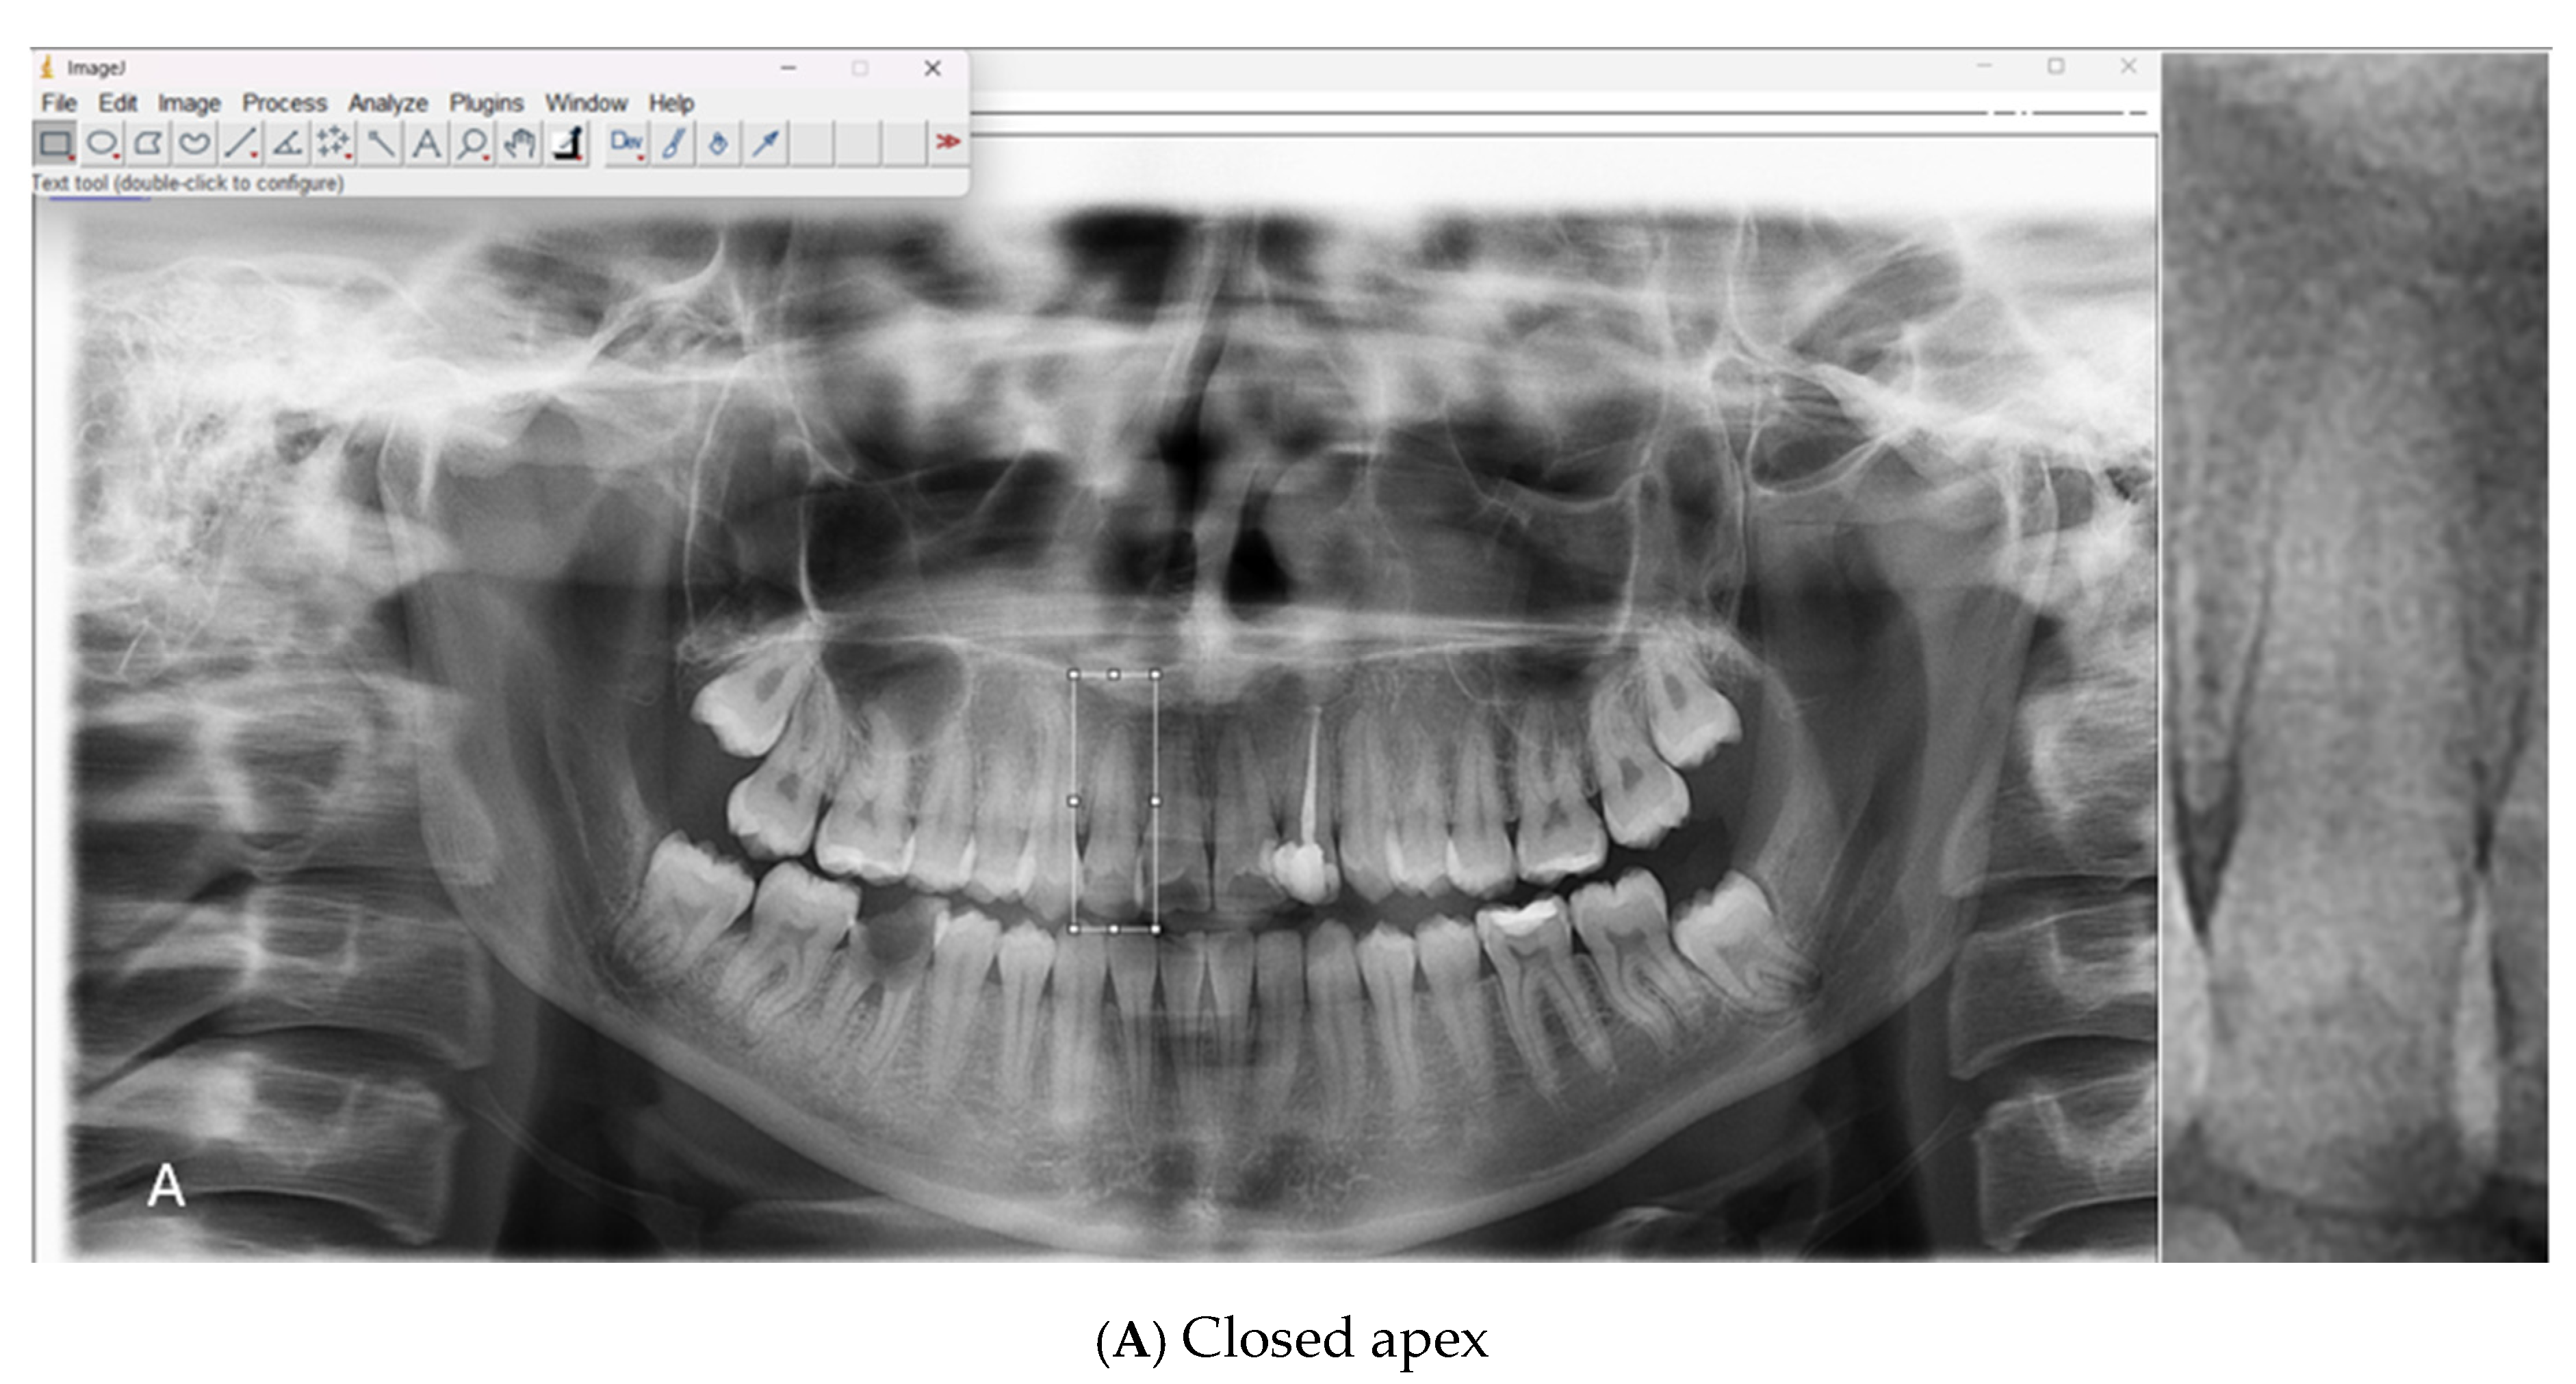

All scans were acquired using a Carestream Dental CS 8100 unit (LLC, 2019) under standard exposure protocols (68 kV, 8 mA, 66 mGy·cm2, 10.8 s). The original images, stored in JPEG format, were processed using ImageJ software (version 1.54g, National Institutes of Health, Bethesda, MD, USA) The apical regions of the relevant teeth were manually isolated, and the regions of interest (ROIs) were saved in PNG format. A total of 1008 ROI images were included in the dataset, consisting of 500 open apex (class 1) and 508 closed apex (class 2) images (Table 1). Representative examples of panoramic radiographs and cropped ROI images used in this study are shown in Figure 1.

Figure 1. Representative panoramic radiographs and cropped regions of interest (ROIs) showing (A) closed apex and (B) open apex teeth.